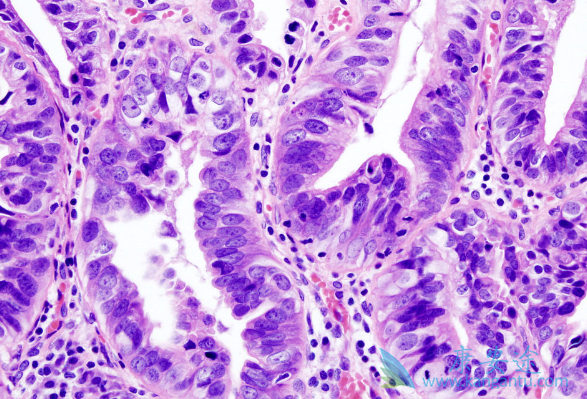

低分化腺癌化疗有效么?低分化腺癌是一种恶性肿瘤的腺癌,对于低分化腺癌,主要的治疗方法是手术、化疗和生物治疗。所以化疗对低分化腺癌是有效的。